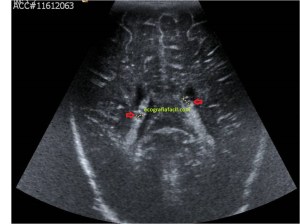

En la imagen 3 ves una imagen de un lipoma, mide 7 cms, la huella de la sonda mide 5cms, la «panoramic view» posee una regla centimetrada que sigue el contorno de la imagen, justo en la profundidad de la misma y lo marca la flecha amarilla. La profundidad la marca la flecha roja y la flecha blanca marca el rango centimetral de los 5cms, fíjate que la línea blanca es ligeramente mayor cada 5 cms. Sirve de referencia, como en la imagen 4 donde ves una colección en el glúteo de más de 10 cms.